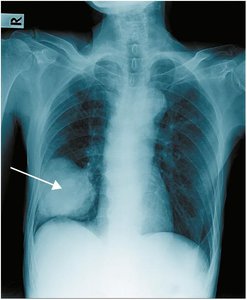

Chest radiography (CXR): X-ray imaging of the lungs

Diseases affecting the lungs include pneumonia, pulmonary edema, pulmonary embolism, tuberculosis, and cystic fibrosis. Pneumonia is an infection of the lung lobes, causing fluid and white blood cells to fill passages. Pulmonary embolism is a blockage of a pulmonary artery by an embolus.

Pneumonia: Bacterial, viral, aspiration, lobar, panlobar, pneumococcal, walking pneumonia